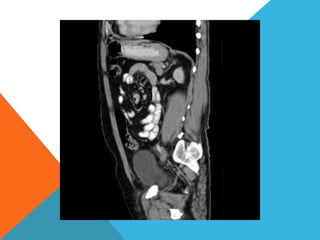

El paciente presentó síntomas de sangrado digestivo y pérdida de peso. Exámenes revelaron gastritis crónica asociada a H. pylori. Un tumor fue descubierto en una colonoscopia normal. La cirugía removió un tumor fibroide solitario, una rara neoplasia mesenquimal que usualmente crece lento y tiene bajo potencial de malignidad. El pronóstico después de la remoción quirúrgica es generalmente bueno.